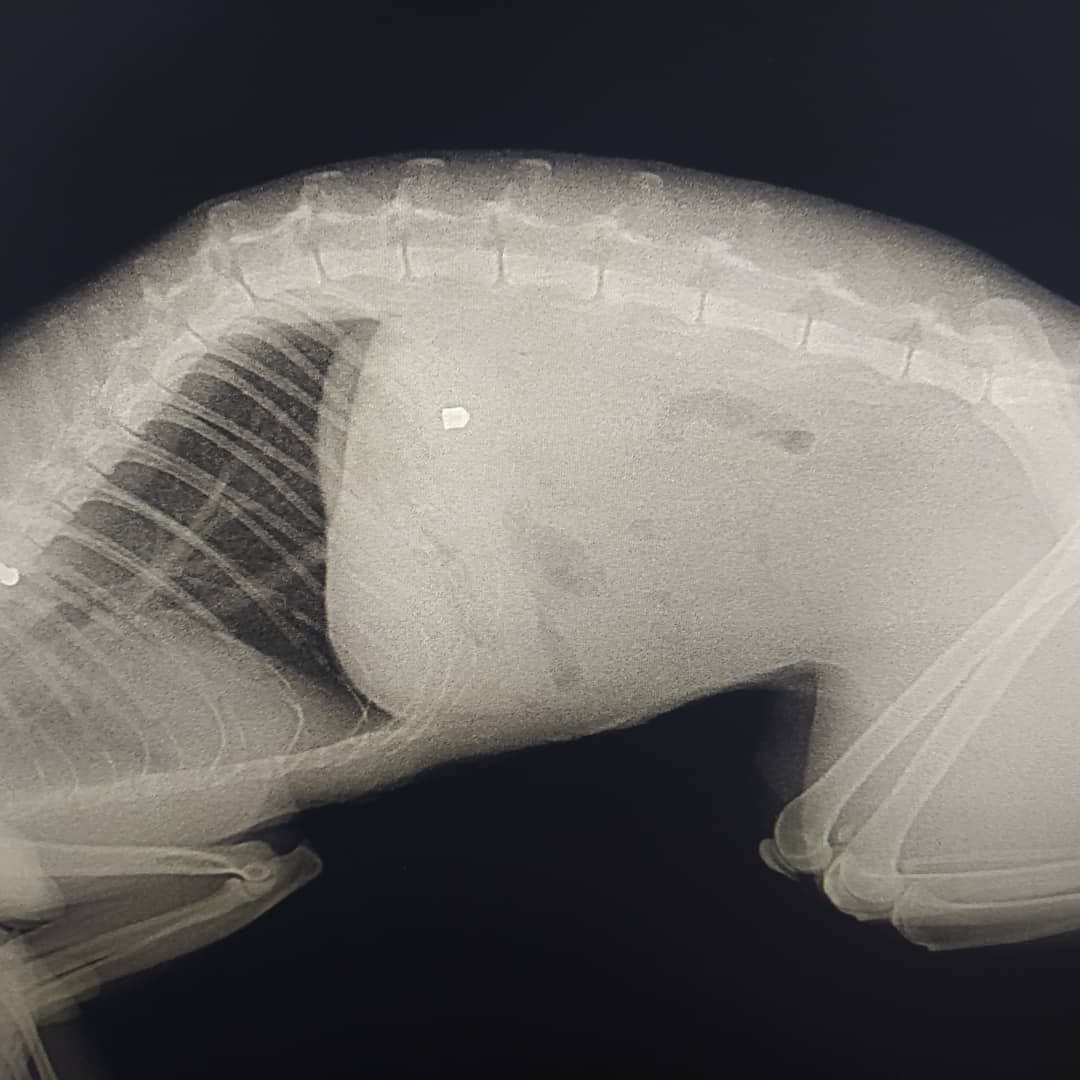

"Вчора кіт ввечері прийшов з раною на животі. Ми повезли його в клініку. Там сказали, що це постріл з воздушки і що ми не перші, хто до них звертається з такою проблемою з нашого району", - йдеться в повідомленні.

Це вже восьмий подібний випадок в районі. Коту надали допомогу, потім провели операцію в іншій лікарні. Воздушка виявилася незвичайною, шансів було всього 20%. На щастя, все пройшло успішно, але коту знадобиться багато часу на відновлення.